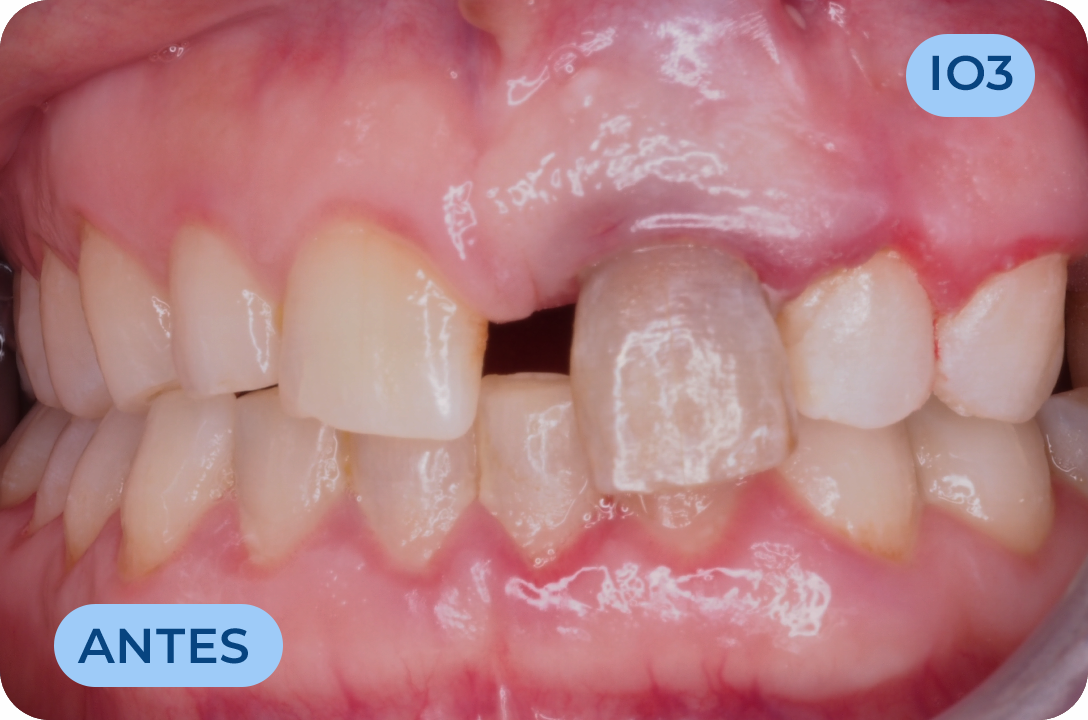

Ortodontia

É a especialidade da Medicina Dentária que se debruça sobre o estudo e correção das más posições dentárias e dos maxilares. Atualmente é possível tratar pacientes de todas as idades, no entanto a 1ª consulta deve ser realizada ainda na infância para intercetar eventuais problemas de desenvolvimento esquelético e funcional.